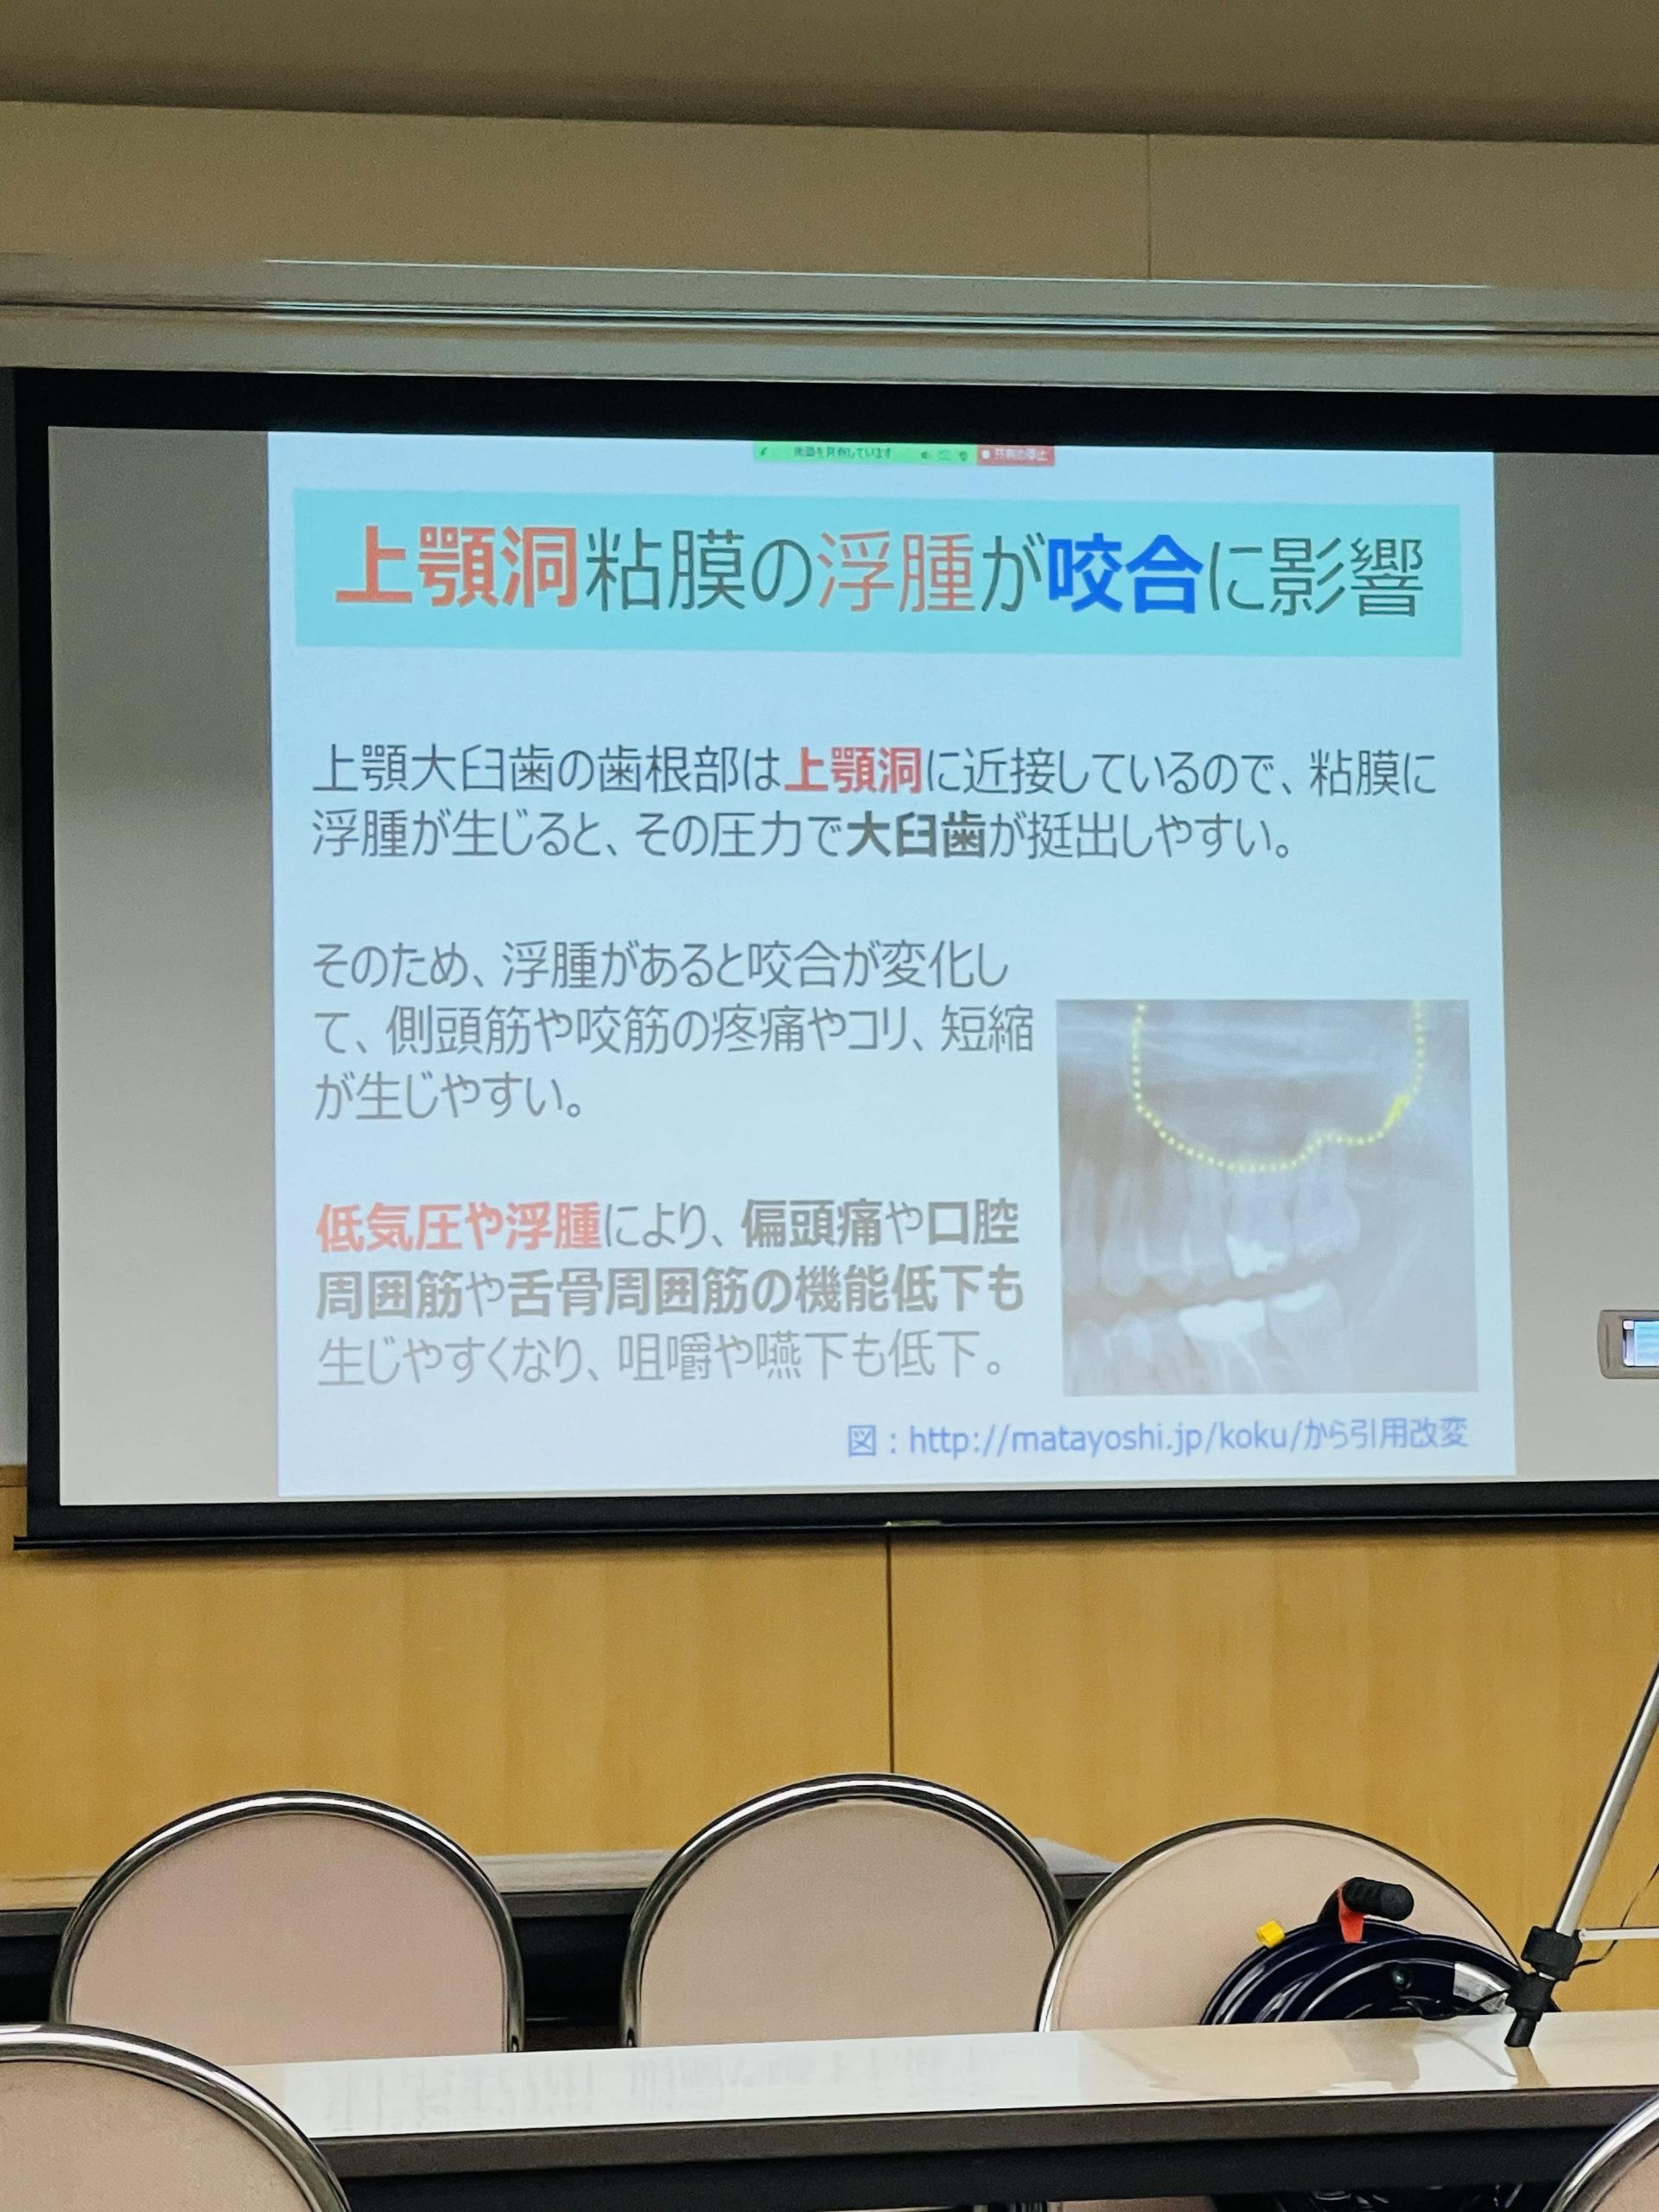

咀嚼ができにくかったりした場合は唾液の分泌が低下しますので補綴物を作り義歯やインプラントなど適正な嚙み合わせを作り、歯ぎしり食いしばりなどには噛み合わせ調整とマウスピースで対処します。

治療してもどんどん進行する歯周病は頻繫な定期健診で歯石や汚れを取り除き、唾液分泌の低下や歯ぎしり食いしばりなどこれらの問題には免疫力、血流、ストレス、抗酸化力が関わってきます。